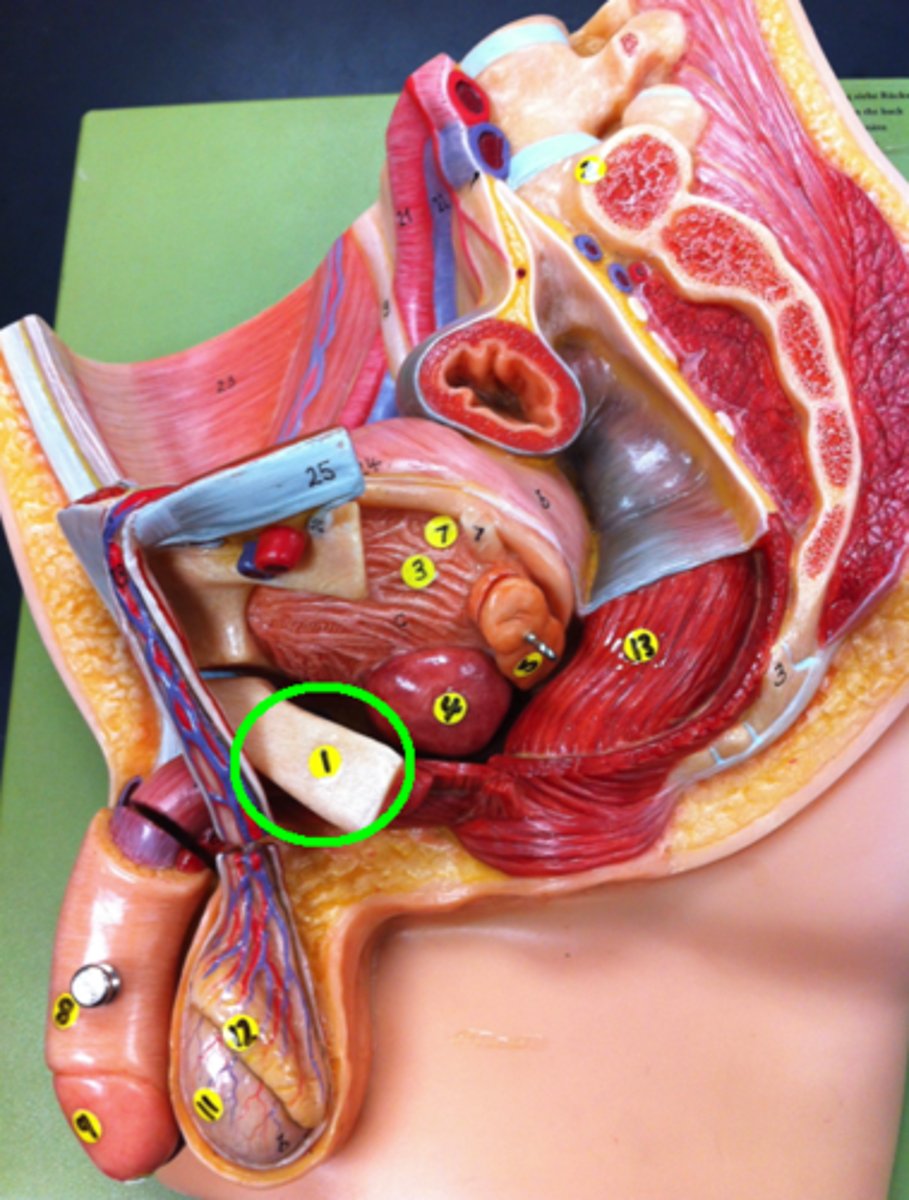

Pubic Bone

Prostate Gland

Ureter